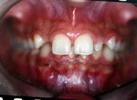

Sınıf 3 Malokluzyonlar

Sınıf 2 Malokluzyonlar

Ortodontik Malokluzyonlar